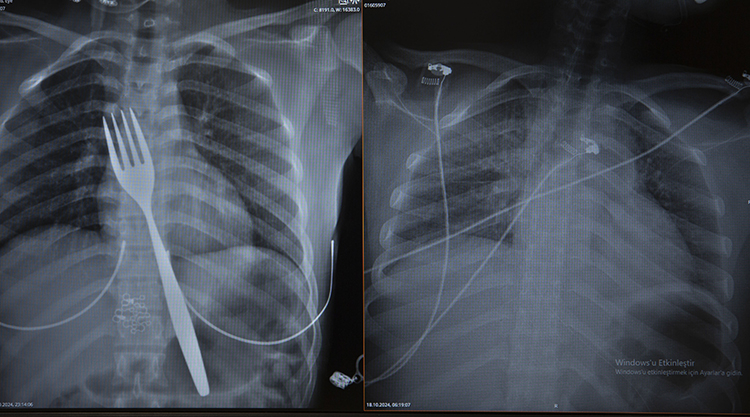

Uzmanlar endoskopi yaparak çatalı ağızdan çıkarmayı denedi. Fakat yemek ve soluk borusuna zarar verme ihtimalinden dolayı midenin kesilerek çatalın çıkarılmasına karar verildi.

ADÜ Tıp Fakültesi Göğüs Cerrahisi Ana Bilim Dalı Öğretim Üyesi Dr. Salih Çokpınar ve Genel Cerrahi Ana Bilim Dalı Dr. Öğretim Üyesi Akay Edizsoy koordinasyonundaki operasyonla midede kesi açılarak çatal çıkarıldı.

"Biz en çok bu yüzden tedirgin olduk. Ama ciddi bir yaralanma olmadığını da yapılan endoskopiyle gördük. Endoskopi ile çıkarılamadı çünkü oldukça büyüktü ve endoskopik aletler için uygun değildi. Bu büyük bir yemek çatalı olduğu için kendi ağırlığı da var. Bir çivi gibi, iğne gibi tutulup çekilemiyor. Bundan dolayı karında yapılan kesi ile mideye ulaşıp midenin içinden bunu çıkarmak şeklinde bir strateji izledik. Yaptığımız bu ameliyatla da bu çatalı oradan çıkarabildik."